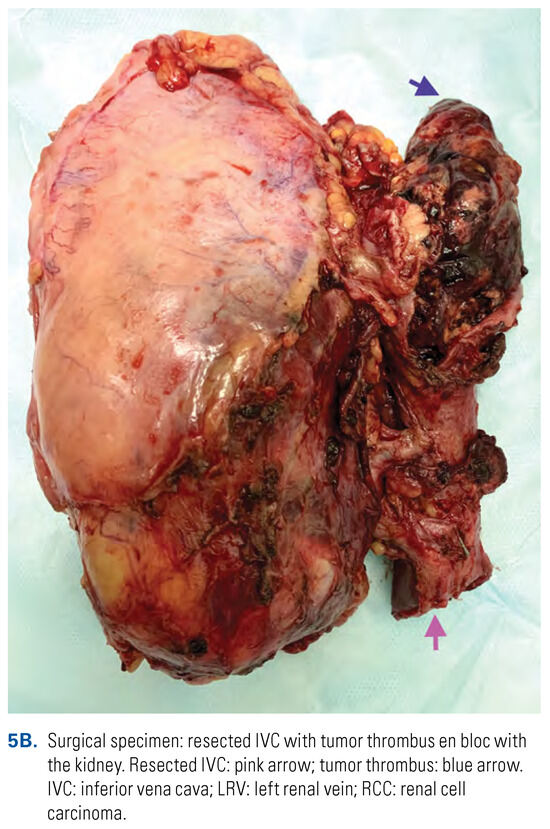

The suprarenal IVC can be safely resected with ligation of the left renal vein in patients with right-sided RCC with VTT. The collateral venous return from the left kidney is sufficient to preserve normal renal function. Thus, resection of the IVC en bloc with rightsided RCC and tumor thrombus from the level of the major hepatic veins to the level of IVC bifurcation (en bloc cavectomy) can be performed without reconstruction[20,48] (Figure 5).

Figure 5. En bloc resection of the IVC with RCC and associated caval thrombus.